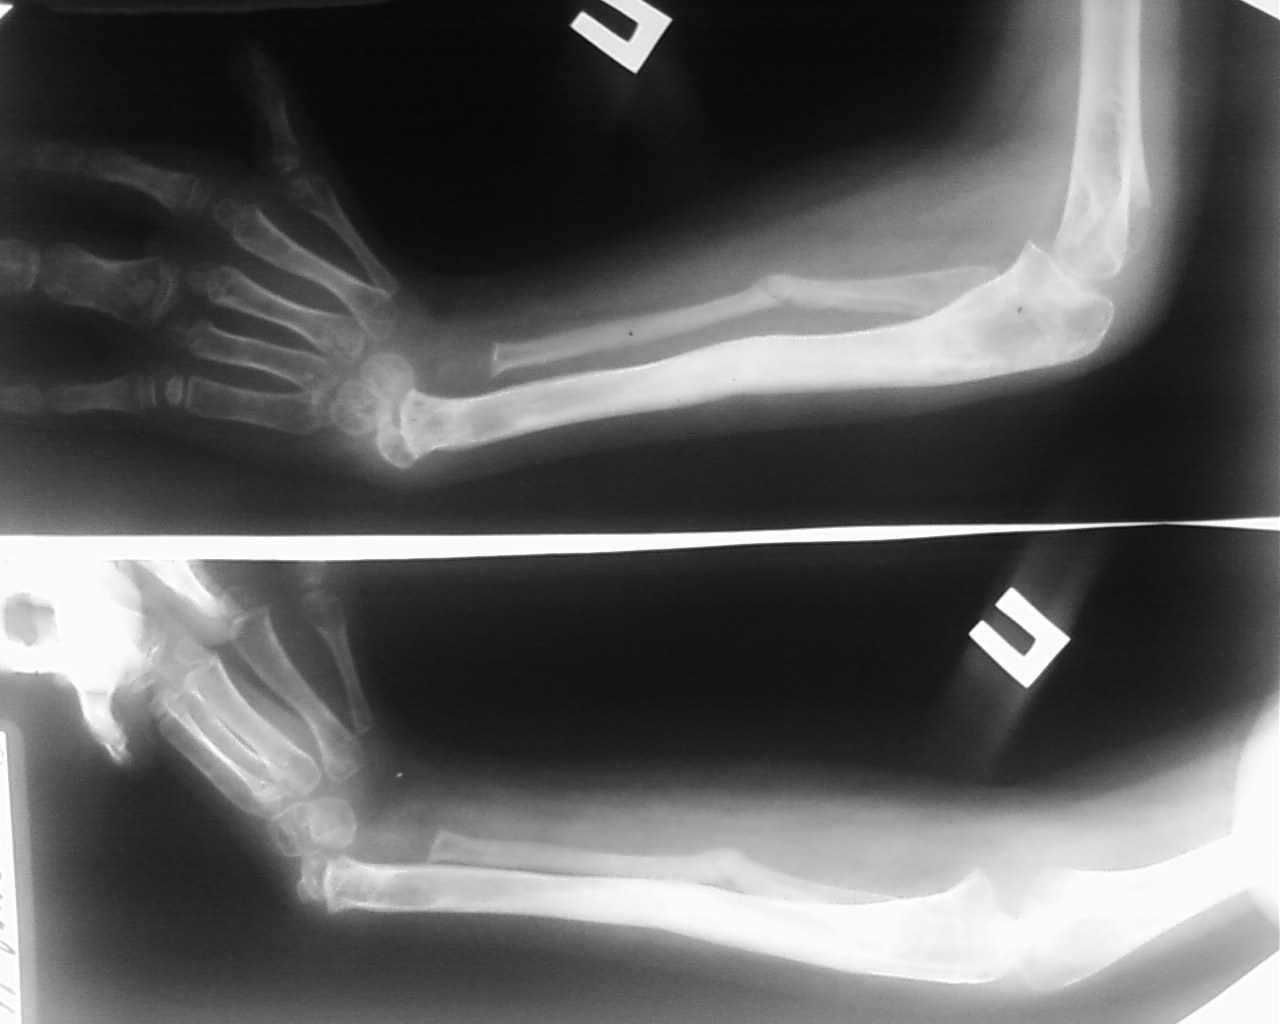

Ребёнок Д.9 лет, клинический диагноз врожденная правосторонняя лучевая косорукость первой степени.

В мае 2009 года проведено удлинение обеих костей правого предплечья в аппарате Илизарова на 4 см, в процессе дистракции был разрыв регенерата, произведена компрессия в аппарате структура кости восстановлена. Сохраняется порочное положение кисти

В настоящее время наложен аппарат внешней фиксации на правую локтевую кость и третью пястную кость, с целью устранения порочного положения правого кистевого сустава.Уважаемые коллеги, помогите определиться с дальнейшей тактикой лечения данного ребенка.С уважением коллектив ТОО КДКБ г. Ставрополя.